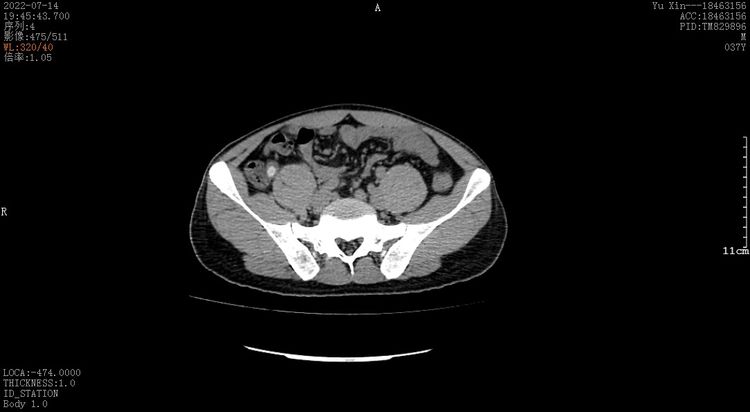

患者为阜阳市某医院的一名年轻医生,暴饮暴食后出现转移性右下腹疼痛,腹痛难忍,此后数十小时滴水未进,还出现了恶心、呕吐等症状,腹部CT提示阑尾明显肿大,可见大量粪石,血常规提示白细胞13.9*10^9/L,打算在其医院行急诊阑尾炎手术切除,偶然了解到市二院消化内科既往有内镜下阑尾炎冲洗术治疗成功的案例,于是选择到市二院进行内镜下微创治疗。消化内科主任马超接诊后,完善相关检查,并征得患者及家属同意后,联系消化内镜中心,拟行逆行性阑尾炎治疗术。